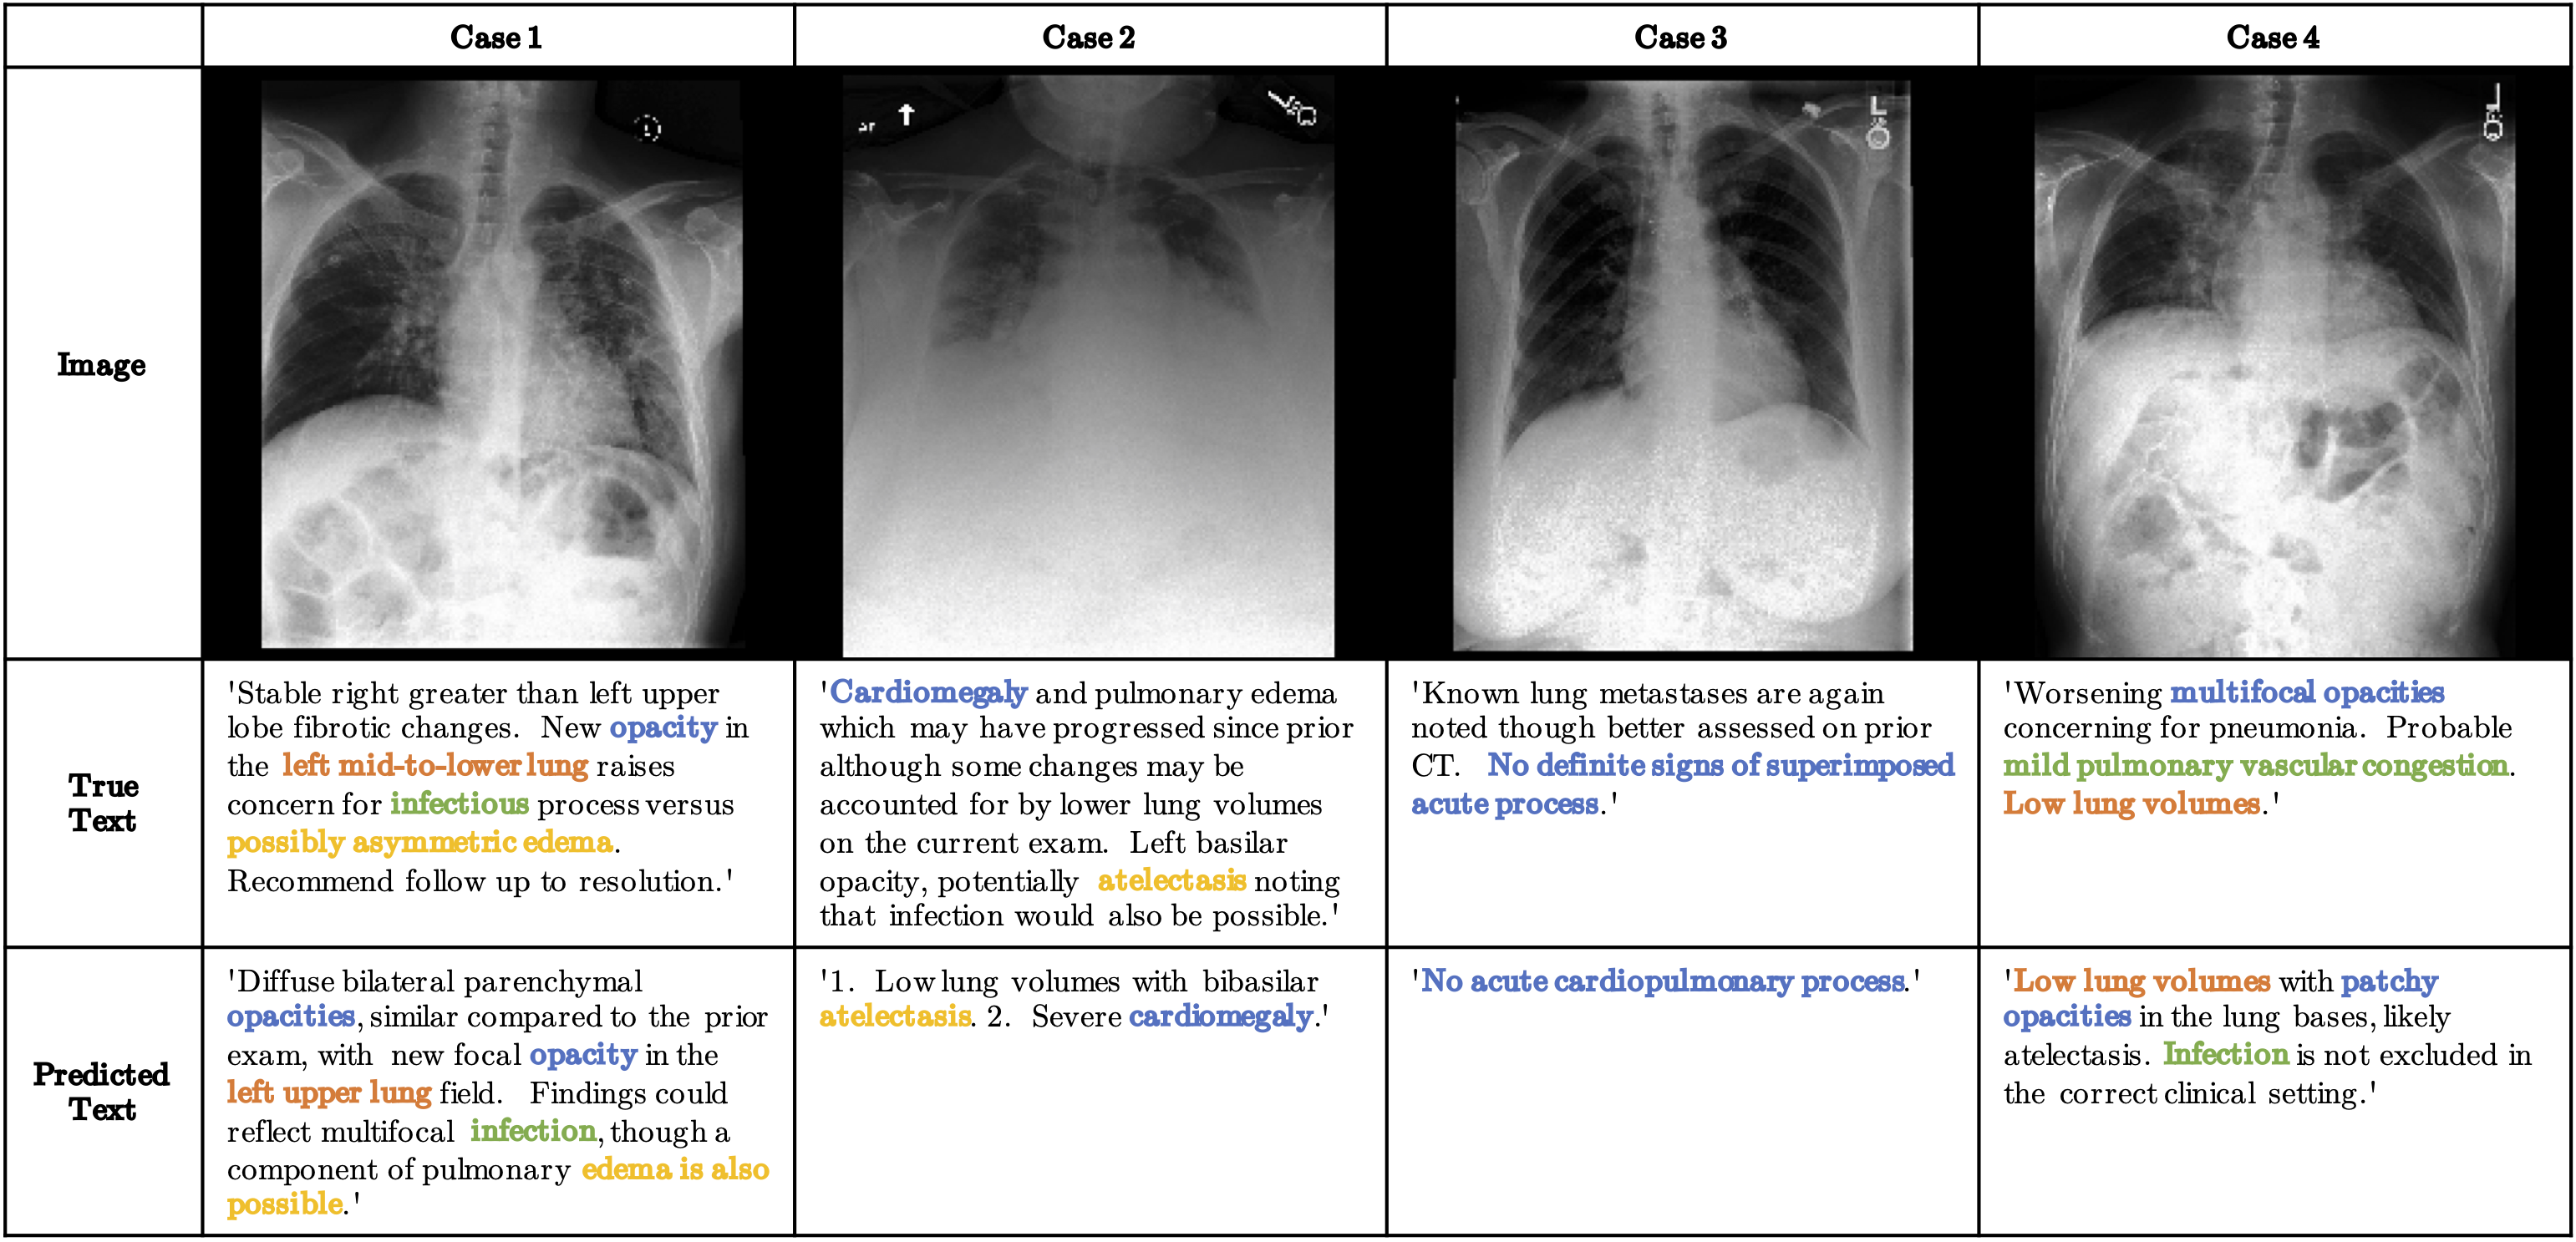

RATCHET: RAdiological Text Captioning for Human Examined Thoraxes

RATCHET is a Medical Transformer for Chest X-ray Diagnosis and Reporting. Based on the architecture featured in Attention Is All You Need. This network is trained and validated on the MIMIC-CXR v2.0.0 dataset.